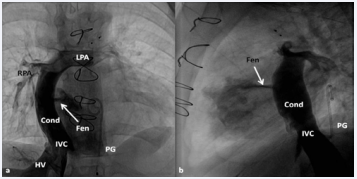

Figure 34 Selected cine frames in postero–anterior (a) and lateral (b) views, demonstrating Stage IIIA Fontan procedure diverting the inferior vena caval (IVC) flow into the pulmonary arteries via a nonvalved conduit (Cond). Flow across the fenestration (Fen) is shown by arrows in a and b. HV, hepatic veins; LPA, left pulmonary artery; PG, pigtail catheter in the descending aorta; RPA, right pulmonary artery [82].

Stage III - Fontan/Kruetzer Procedure: During this final stage, the IVC flow is diverted into the PA along with creation of a fenestration. We arbitrarily divided these procedures into Stage IIIA (diversion of IVC into the PA) and Stage IIIB (closure of the fenestration) [55,82].

Stage IIIA: In the Stage IIIA, the TCPC is accomplished by redirecting the IVC flow into the PA either by a lateral tunnel [41,83], or by an extra-cardiac, non-valved conduit [45,84]. This surgery is typically carried out between the ages of 1 and 2 years, frequently 1 year after the bidirectional Glenn (Stage II). At the present time, most surgeons seem to favor an extra-cardiac conduit to achieve the final stage of Fontan. It also appears that the majority of surgeons create a fenestration, 4-6 mm in size, between the conduit and the atria [46]. Whereas fenestration during the Fontan surgery was originally suggested for high-risk patients [46,47], most surgeons and pediatric intensivists appear to prefer fenestration, since creation of fenestration during the Fontan decreases mortality rate and lessens the morbidity during the immediate postoperative period [82].

Echocardiographic and angiographic examples of the Fontan procedure are shown in Figures 29 to 34.